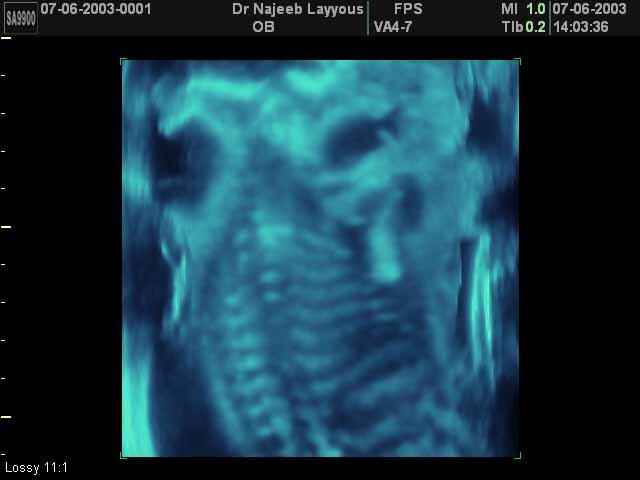

- 3D Photos échographie du squelette du fœtus

3D Photos échographie du squelette du fœtus | Dr N Layyous